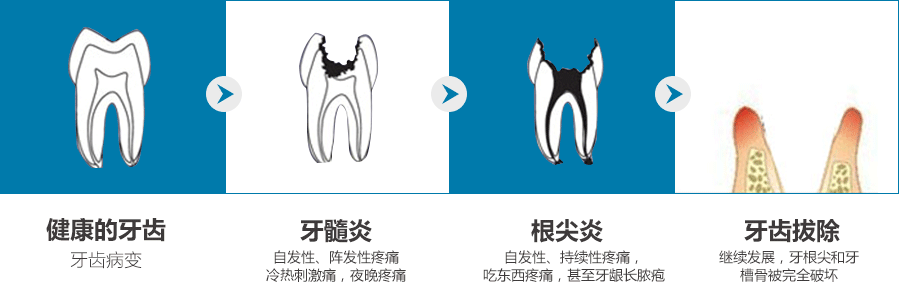

牙痛怎么快速止痛

牙痛不是病,痛起来真要命。牙痛是一种常见疾病。牙痛大多由牙龈炎和牙周炎、龋齿(蛀牙)或折裂牙而导致牙髓(牙神经)感染所引起的。康贝佳口腔提醒:引起牙痛的原因很多,... [详情]

根管治疗

安全微痛,根治多种牙齿病症

适应症:

急性或慢性牙髓炎、根尖炎症、牙髓暴露感染、意外伤及牙神经